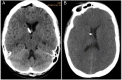

Figure 2.

Non-contrast head CT Findings. A, Immediate postoperative non-contrast head CT with good placement of the Ommaya catheter. B, Repeat non-contrast head CT 19 hours after Ommaya placement and IT MTX administration.